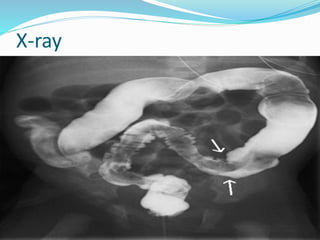

X-ray

Diagnosis